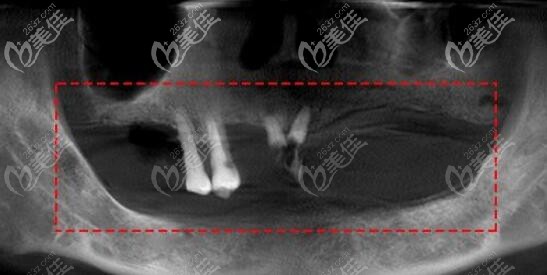

长时间缺牙后牙槽的骨吸收情况:

有的牙槽骨吸收比较多的顾客还要行植骨,才能骨量的充足,提高种植牙的。